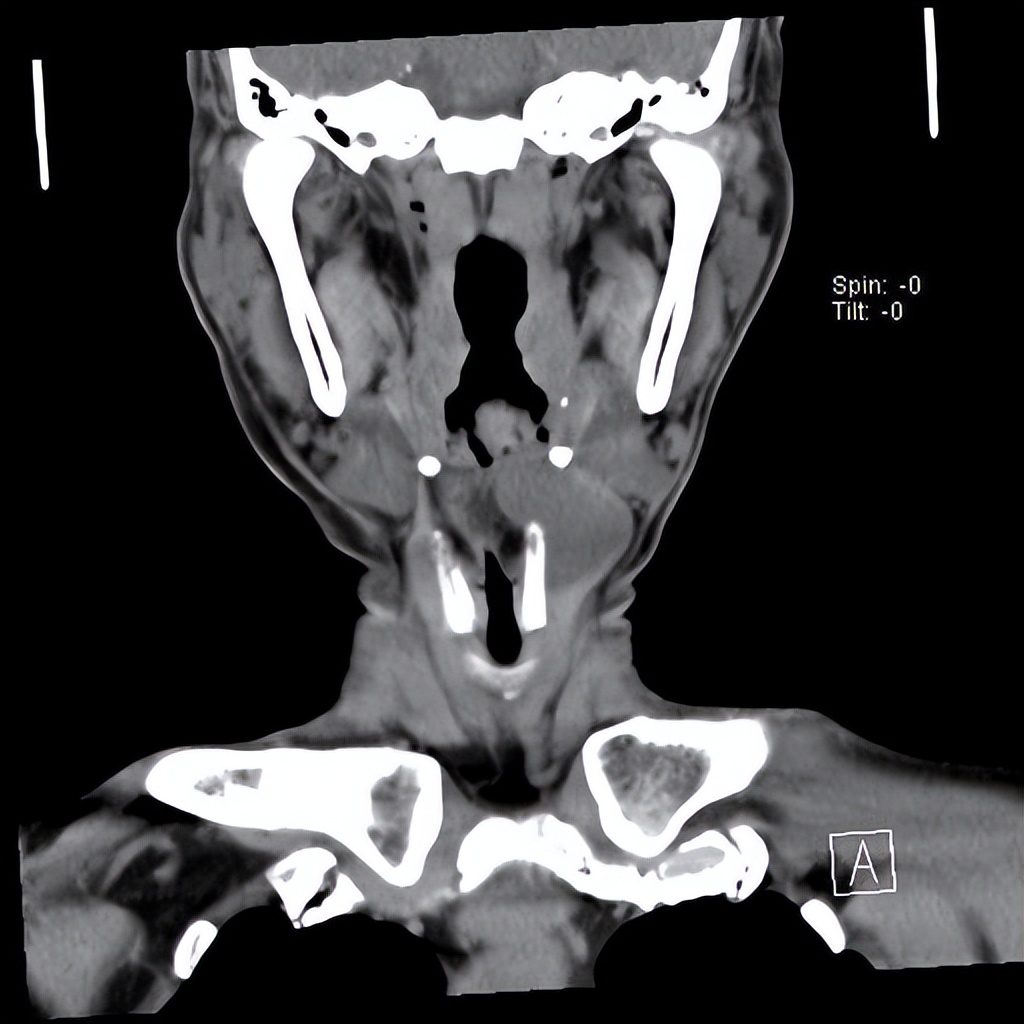

来自广东梅州的管叔,最近发现颈部肿物2周,不痒,不痛,自觉问题不大。但是肿物越来越大了,在家人的劝说下来到佛山复星禅诚医院耳鼻喉做了检查发现是颈部的先天性囊肿。

颈部肿物目前做小切口内镜微创手术比较适合,这样既能切除干净肿物,也会兼顾美观。关于颈部肿物如果您有任何的问题,欢迎留言和耳鼻喉郑立岗医生进一步交流。